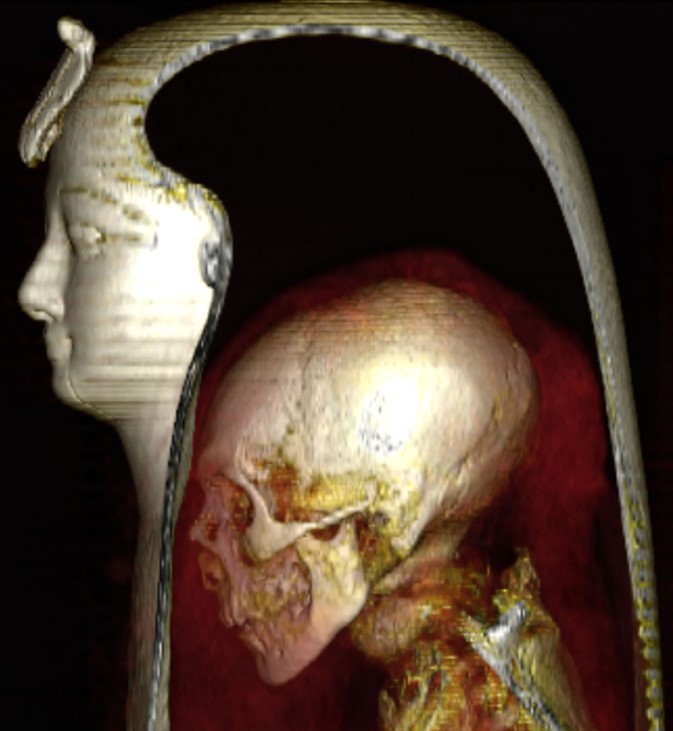

Xác ướp của [pharaoh] Amenhotep I với mặt nạ bằng gỗ phủ sơn và giấy carton. (Ảnh: Đăng dưới sự cho phép của Sahar N. Saleem và Zahi Hawass)

Xác ướp đã bị xâm phạm bởi các kẻ đột nhập mộ từ rất lâu trước đây, rồi lại được các tu sĩ dưới Vương triều thứ 21 cải táng. Việc cải táng ấy được thực hiện trang trọng cùng những vòng hoa màu vàng, đỏ và xanh, và cả một chiếc mặt nạ còn nguyên vẹn làm bằng giấy carton và gỗ phủ sơn được trang trí với đôi mắt cẩn đá obsidian và một con rắn hổ mang ở phần trán.

Xác ướp của [pharaoh] Amenhotep I được mô tả là có khuôn mặt trái xoan với đôi mắt trũng sâu và hai má hóp lại. Ông có phần mũi nhỏ, hẹp và tẹt, hàm răng hơi đưa ra ngoài. Ông cũng có đôi tai nhỏ với một chiếc khuyên nhỏ ở dái tai trái. Đáng chú ý là ông được phát hiện có một vài lọn tóc cuộn ở phía sau và hai bên đầu.

Hình ảnh chụp CT ba chiều phần đầu của xác ướp [pharaoh] Amenhotep I. (Ảnh: Đăng dưới sự cho phép của Sahar N. Saleem và Zahi Hawass)

Hình ảnh CT ba chiều kỹ thuật số của khuôn mặt không được bao phủ của xác ướp [pharaoh] Amenhotep I. (Ảnh: Đăng dưới sự cho phép của Sahar N. Saleem và Zahi Hawass)